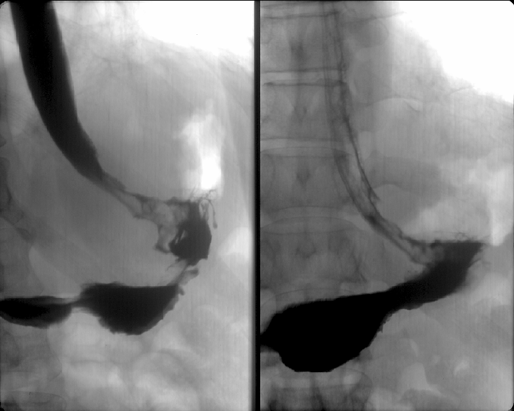

Во-вторых, своеобразие рентгено-эндоскопических данных — диффузное изменение стенки желудка с развитием ригидности, циркулярного сужения (желудок изменен по типу кожаного сосуда) (рис. 1), утолщения стенок и плохого расправления складок на фоне инсуфляции воздуха. Своеобразие морфологической картины — гнездное включение опухолевых клеток в виде очагов в слизистую оболочку желудка с диффузной инфильтрацией слоев на фоне выраженной стромальной реакции с развитием интерстициального фиброза. Отличны подходы к тактике хирургического и комбинированного лечения. Однако главным отличием данной формы рака желудка является крайне неблагоприятный прогноз. Абсолютное большинство пациентов поступают на лечение в распространенных стадиях заболевания. Истинно радикальные вмешательства удается выполнить крайне редко, что отражается на отдаленных результатах — 5 лет наблюдения переживает не более 5% пациентов. Основным видом прогрессирования после радикального лечения является интраперитонеальный рецидив в виде канцероматоза брюшины.

Рисунок 1. Тотальный рак желудка

Для исследования характера опухолевой инфильтрации по желудку всем больным выполняются ;рентгенологическое и эндоскопическое ;исследования. ;Только комбинация обоих методов позволяет оценить характер опухолевой инфильтрации по желудку с возможным переходом на смежные структуры ЖКТ по протяжению (пищевод, двенадцатиперстная кишка) и классифицировать тип опухолевого роста, что является интегральным показателем, объединяющим данные рентгенологического и эндоскопического обследования.

Рентгенологическое обследование целесообразно проводить комплексно, используя ;тугое заполнение и двойное контрастирование. Первый метод наиболее информативен при экзофитных опухолях, второй (включающий сочетанное применение ;бария с шипучими субстанциями ;на фоне релаксации стенки желудка с применением ;глюкагона) — позволяет оценить интрамуральную инфильтрацию желудочной стенки и вовлечение смежных структур (пищевод, двенадцатиперстная кишка) на протяжении. Основным преимуществом метода двойного контрастирования является возможность детального изучения минимальных изменений слизистой (за счет расправления желудка газом), а также — тщательного изучения проксимального отдела желудка, что невозможно при применении лишь тугого заполнения.